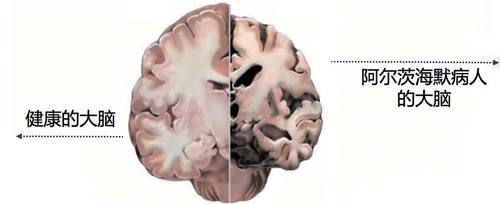

阿尔茨海默病是一种神经退行性疾病,一般65岁以上起病。它会慢慢侵袭我们的大脑,把正常饱满的大脑逐渐变成“风干的核桃”,实质体积逐渐变小,沟壑变深,不断退化。临床上表现为记忆力减退,语言功能障碍,执行功能障碍,思考能力下降,自理能力也将受到影响。随着疾病发展,还会出现狂躁易怒攻击等精神行为异常。